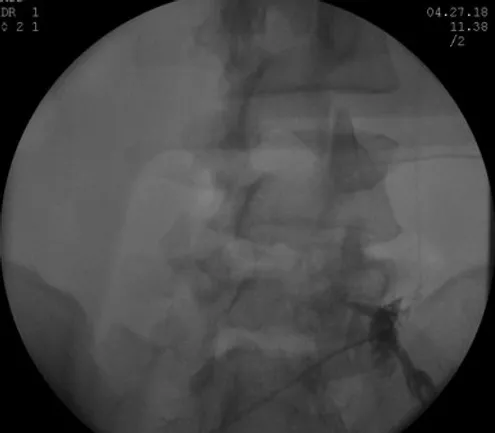

Decided to proceed with Right sided L5 and S1 Transforaminal Epidural Steroid Injections

Transforaminal Epidural Steroid Injection

First Lumbar Bilateral L5-S1 Transforaminal Epidural Steroid Injection 11/01/2016 > 30% Relief

Second Lumbar Bilateral L5-S1 Transforaminal Epidural Steroid Injection 11/29/2016 > 50% Relief

Third Lumbar Bilateral L5-S1 Transforaminal Epidural Steroid Injection 12/27/2016 > 70% Relie